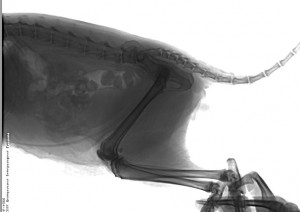

К счастью обзорные снимки не выявили внутренних повреждений , при осмотре температура тела в норме , но уши и глаза в очень плохом состоянии . Коту назначен необходимый курс лечения , после которого мы надеемся он быстро поправиться и восстановиться .

За счет средств Фонда найденному коту была оказана ветеринарная помощь в обследовании и осмотре, лечении, проведении ренгенологических снимков и покупке части необходимых ветеринарных препаратов.